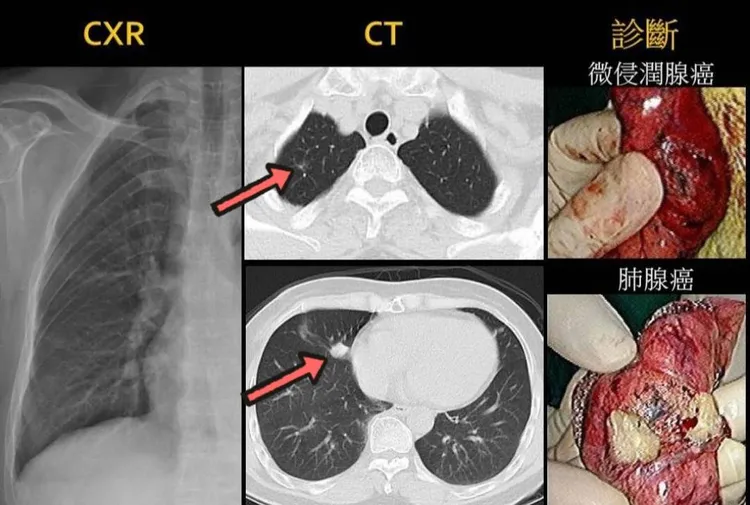

林阿嬤X光片無異常,斷層片顯現右中肺葉一顆1.2cm肺腺癌,右上肺葉一顆0.4cm微浸潤腺癌。阮綜合提供

73歲林阿嬤老伴過世六年,在北部工作的兒女假日輪流回來陪伴,由於不捨南北奔波的孩子屢勸她從年輕就容易拉肚子的情況要去做大腸癌篩檢,就來到高雄阮綜合醫院。大腸鏡檢查無異常,但血液癌症指數有4.3(標準3),胸腔外科戴碩瑩醫師醫師安排X光及電腦斷層檢查,結果X光無異常,斷層發現右上肺葉有一顆0.4公分的微浸潤腺癌,與右中肺葉一顆1.2公分的肺腺癌,考慮阿嬤年紀,兩周後由戴醫師以「單孔胸腔鏡」微創手術切除治療,術後血液癌症指數降為1.3,後續追蹤。

腫瘤大到1分以上才會被X光偵測到,低劑量電腦斷層可以偵測3~4mm大小的肺結節,在斷層偵測到的越小,越屬於早期範圍,治療上簡單安全又可能根治。反過來,X光檢查偵測不到1公分以下的腫瘤,若病灶位置在不易判讀的死角,會造成診斷治療延遲,延遲3至5年後,原本1公分可能長到7公分以上,甚至是第四期肋膜轉移或遠端轉移,晚期惡化的腫瘤,通常難以回天。